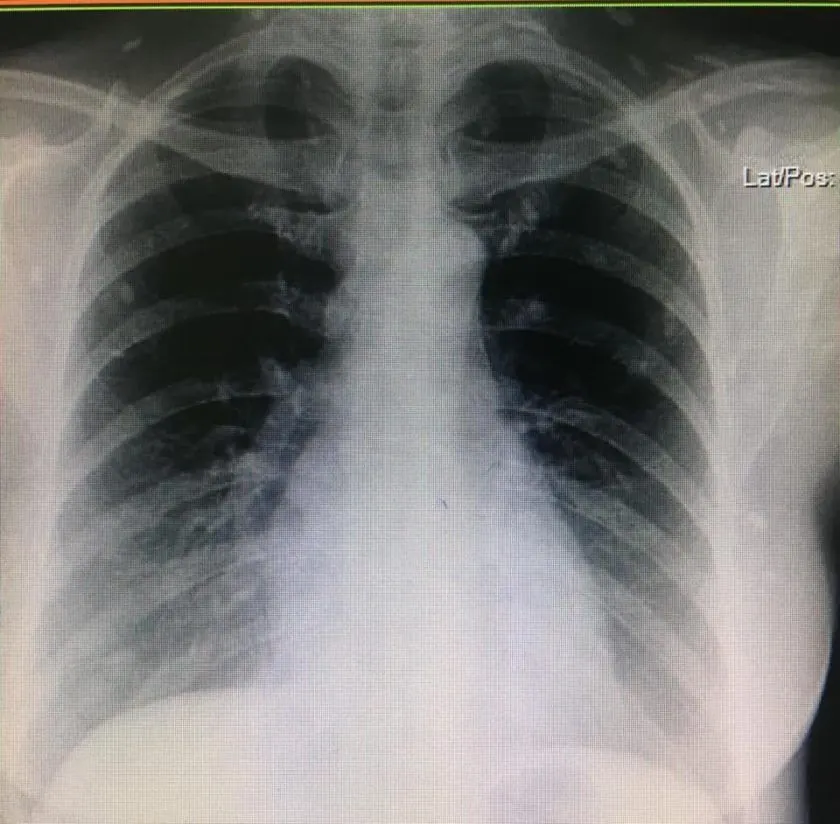

จากภาพทางด้านล่างคือ x–ray ตรงขา สะโพก แล้วที่ขาวๆ ที่กระจายทั่วกล้ามเนื้อ คือตัวอ่อนพยาธิตืดหมูที่ไชเข้าสู่ร่างกายแล้วระบบภูมิคุ้มกันของร่างกายก็รับมือกับมัน จนเกิดหินปูนมาเกาะ เคยเห็นแต่ในตำรา หมอเจ้าของโพสต์ได้เจอของจริงจะๆเลย

ส่วนสาเหตุเกิดจากการกินเมนูที่ใส่หมูดิบแล้วมีตัวอ่อนพยาธิในนั้น หรือกินผักที่ปนเปื้อนไข่ของพยาธิชนิดนี้ แล้วพอตัวอ่อนมันไชเข้าร่างกาย ก็จะไปแถวกล้ามเนื้อมั่ง หรือเข้าสมอง จากนั้นก็จะกลายเป็นหินปูนแบบที่เห็นแล้วทำให้เกิดอาการต่างๆนานา บางคนที่ไชเข้าสมอง ก็จะไปหาหมอด้วยอาการ ปวดหัวเรื้อรัง ชักเกร็ง